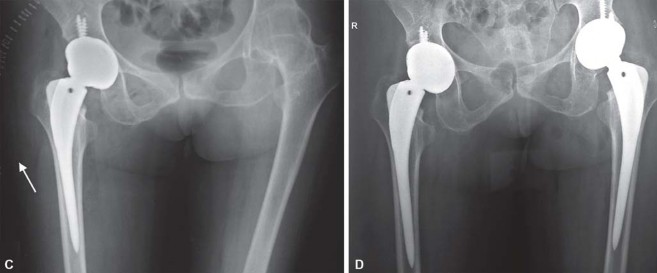

يميل مرضى التهاب المفاصل الروماتويدي اليفعي إلى امتلاك قناة نخاعية فخذية ضيقة جدًا مع عدم توافق بين قطر القناة القريبة والبعيدة. يمكن أن يختلف التجويف الحقي من النوع المشوه (كما يظهر في الشكل 29.1) إلى النوع المنغمس (كما يظهر في الشكل 29.2) أو قد يكون مفصل ورك ملتحم (كما يظهر في الشكل 29.3).

نمط الورك المشوه

نمط انغماس الورك

انصهار ثنائي في مفصل الورك بالتهاب المفاصل اليفعي